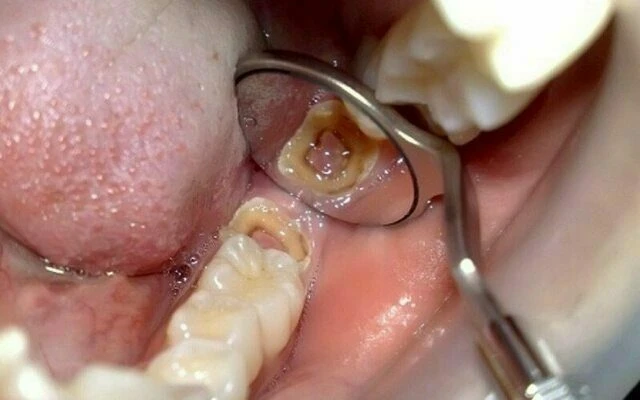

Nguyên nhân gây chết tủy hoặc bệnh lý tủy là gì?

Khi tủy răng bị tổn thương hoặc bị bệnh lý và không thể tự sửa chữa, nó bị viêm và cuối cùng hoại tử. Nguyên nhân thường gặp nhất của chết tủy là sâu răng lan rộng, miếng trám sâu, chấn thương (chẳng hạn va chạm mạnh vào răng), nứt răng, và bệnh lý nha chu hoặc lợi. Khi tủy răng tiếp xúc với vi khuẩn từ sâu răng hoặc nước bọt, nhiễm trùng có thể xảy ra bên trong răng và nếu không được điều trị có thể gây ra nhiễm trùng tại vùng chóp chân răng, hình thành nên áp xe. Cuối cùng xương nâng đỡ răng bị tiêu, đau và sưng thường đi kèm với nhiễm trùng. Nếu không điều trị nội nha, cuối cùng phải nhổ răng.